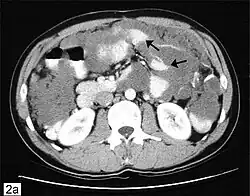

CT scanning is preferred to assess the extent of the tumor in the abdominopelvic cavity, though magnetic resonance imaging can also be used.[28] CT scanning can also be useful for finding omental caking or differentiating fluid from solid tumor in the abdomen, especially in low malignant potential tumors. However, it may not detect smaller tumors. Sometimes, a chest x-ray is used to detect metastases in the chest or pleural effusion. Another test for metastatic disease, though it is infrequently used, is a barium enema, which can show if the rectosigmoid colon is involved in the disease. Positron emission tomography, bone scans, and paracentesis are of limited use; in fact, paracentesis can cause metastases to form at the needle insertion site and may not provide useful results.[29] However, paracentesis can be used in cases where there is no pelvic mass and ascites is still present.[29] A physician suspecting ovarian cancer may also perform mammography or an endometrial biopsy (in the case of abnormal bleeding) to assess the possibility of breast malignancies and endometrial malignancy, respectively. Vaginal ultrasonography is often the first-line imaging study performed when an adnexal mass is found. Several characteristics of an adnexal mass indicate ovarian malignancy; they usually are solid, irregular, multilocular, and/or large; and they typically have papillary features, central vessels, and/or irregular internal septations.[31] However, SCST has no definitive characteristics on radiographic study.[32]

Metastasis in ovarian cancer is very common in the abdomen and occurs via exfoliation, where cancer cells burst through the ovarian capsule and are able to move freely throughout the peritoneal cavity. Ovarian cancer metastases usually grow on the surface of organs rather than the inside; they are also common on the omentum and the peritoneal lining. Cancer cells can also travel through the lymphatic system and metastasize to lymph nodes connected to the ovaries via blood vessels; i.e. the lymph nodes along the infundibulopelvic ligament, the broad ligament, and the round ligament. The most commonly affected groups include the paraaortic, hypogastric, external iliac, obturator, and inguinal lymph nodes. Usually, ovarian cancer does not metastasize to the liver, lung, brain, or kidneys unless it is a recurrent disease; this differentiates ovarian cancer from many other forms of cancer.[29]